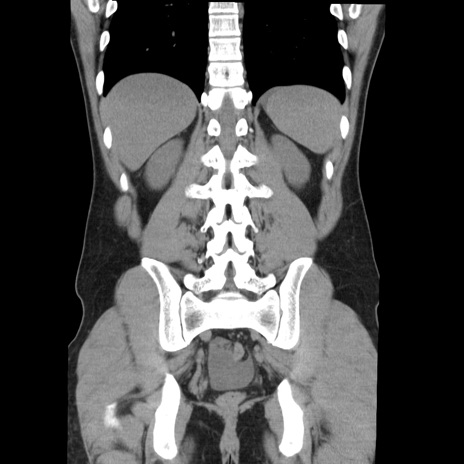

症例36(冠状断像)

【症例】20歳代 男性

【主訴】心窩部痛

【現病歴】今朝より上腹部痛あり。一旦軽快していたが再度出現したため救急要請。昨日夕に白身の魚を含む刺身を食べた。

【身体所見】BP 136/89mmHg、HR 74/min、BT 37.0℃、腹部:膨満、軟、心窩部に圧痛あり。反跳痛なし、筋性防御なし、腸雑音やや亢進あり。

【データ】WBC 17700、CRP 0.48